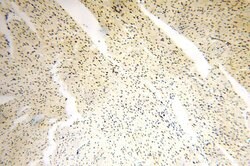

GTF2IRD1 Rabbit anti-Human, Mouse, Rat, Polyclonal, Proteintech

Applications | Immunocytochemistry, Immunofluorescence, Immunohistochemistry (Paraffin), Immunoprecipitation, Western Blot |

Williams-Beuren syndrome (WBS) is a developmental disorder caused by the hemizygous microdeletion on chromosome 7q11.23. WBS is an autosomal domit genetic condition that is characterized by physical, cognitive and behavioral traits. The physical traits associated with WBS include facial dysmorphology, vascular stenoses, growth deficiencies, dental anomalies and neurologic and musculoskeletal abnormalities. Mild retardation, a weakness in visual-spatial skills, anxiety and a short attention span are typical cognitive and behavioral traits of WBS patients. The WBSCR11 gene is located within the WBS deletion and may contribute to the developmental symptoms found in WBS because of a loss of the encoded transcription factor. WBSCR11 is also designated GRF2IRD1, GTF3, Cream1 and MusTRD1 in human and BEN in mouse, due to slight differences in gene structure. WBSCR11 is expressed in all adult tissues as several variants and has discrete spatial and temporal expression during embryogenesis.Specifications